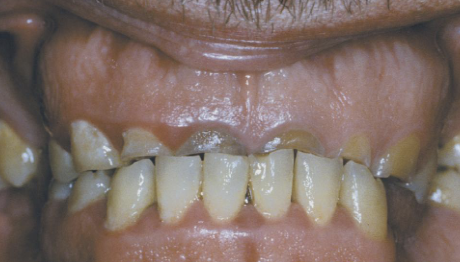

affects both dentition, steel-grey/ translucent/ opalescent crowns, brittle enamel

DGI

DGI radiographic presentation

bulbous crown, cervical constriction, pulp obliteration varies, expanded pulp = shell teeth